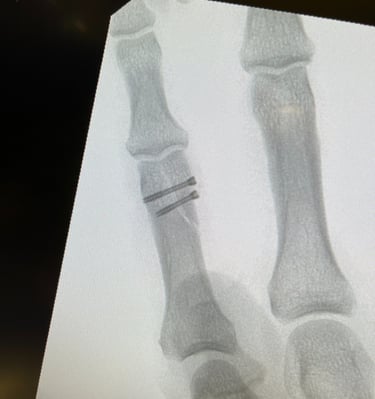

Mi occupo del trattamento delle principali patologie della mano e del polso, sia degenerative che traumatiche. Tratto condizioni frequenti come sindrome del tunnel carpale, dito a scatto, tendiniti e traumatologia della mano e del polso, con approccio conservativo o chirurgico mirato al recupero della funzionalità e alla riduzione del dolore.